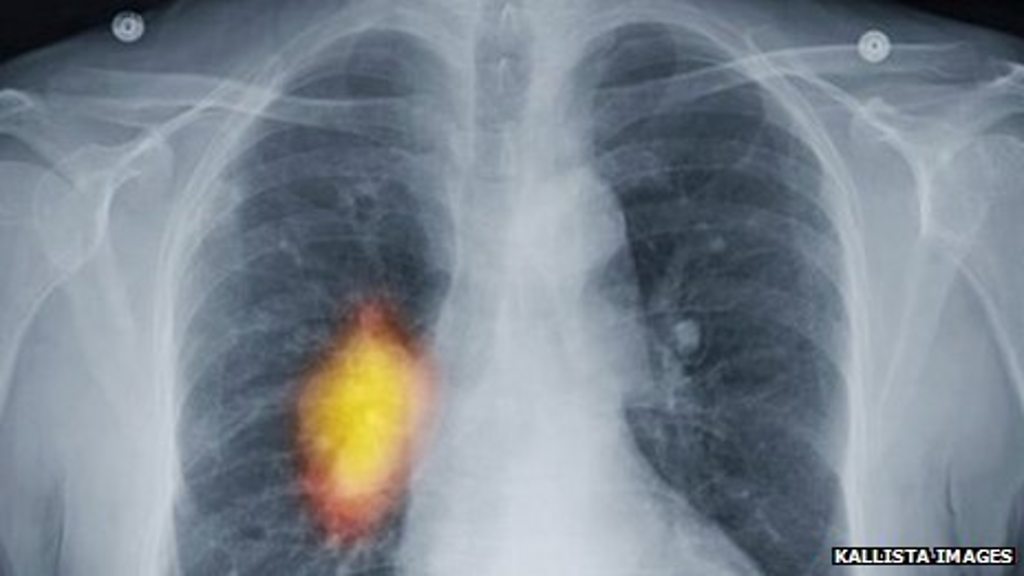

Today's Tom Feilden and Peter Johnson of Cancer Research discuss the Institute of Cancer Research's new centre.